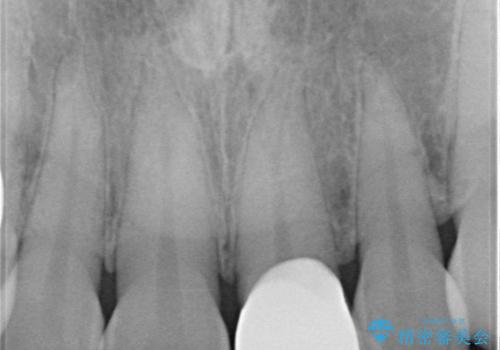

- 以前保険診療で行った前歯を自然できれいなセラミックにしたいと来院された患者様です。

古い材料と虫歯を除去して、土台の形を整え、より自然なオールセラミッククラウンにすることとしました。

セラミックは噛み合わせによっては欠けてしまうことがあるため、その予防でナイトガードを製作しました。